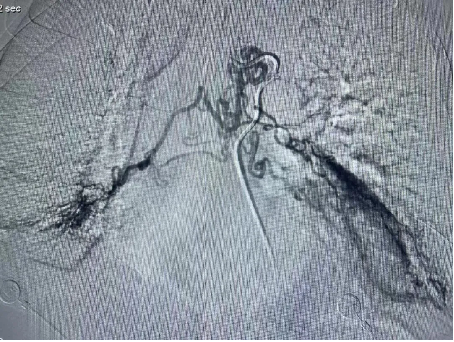

医院呼吸内科团队高度重视患者的治疗,组织全科人员讨论制定个性化治疗方案,通过患者体动脉cta造影检查,明确了包括支气管动脉在内的5支病变血管。经充分术前准备,7月2日晚7点,曹辛瑜副主任在术中精准定位出血病变血管,及时用栓塞剂对病变血管逐个栓塞,完全阻断病变血管血流,痰液立即恢复正常。患者手术顺利,术后恢复良好。支气管动脉栓塞术的应用,大大缩短患者住院时间,且有效降低患者出现大咯血窒息死亡风险。